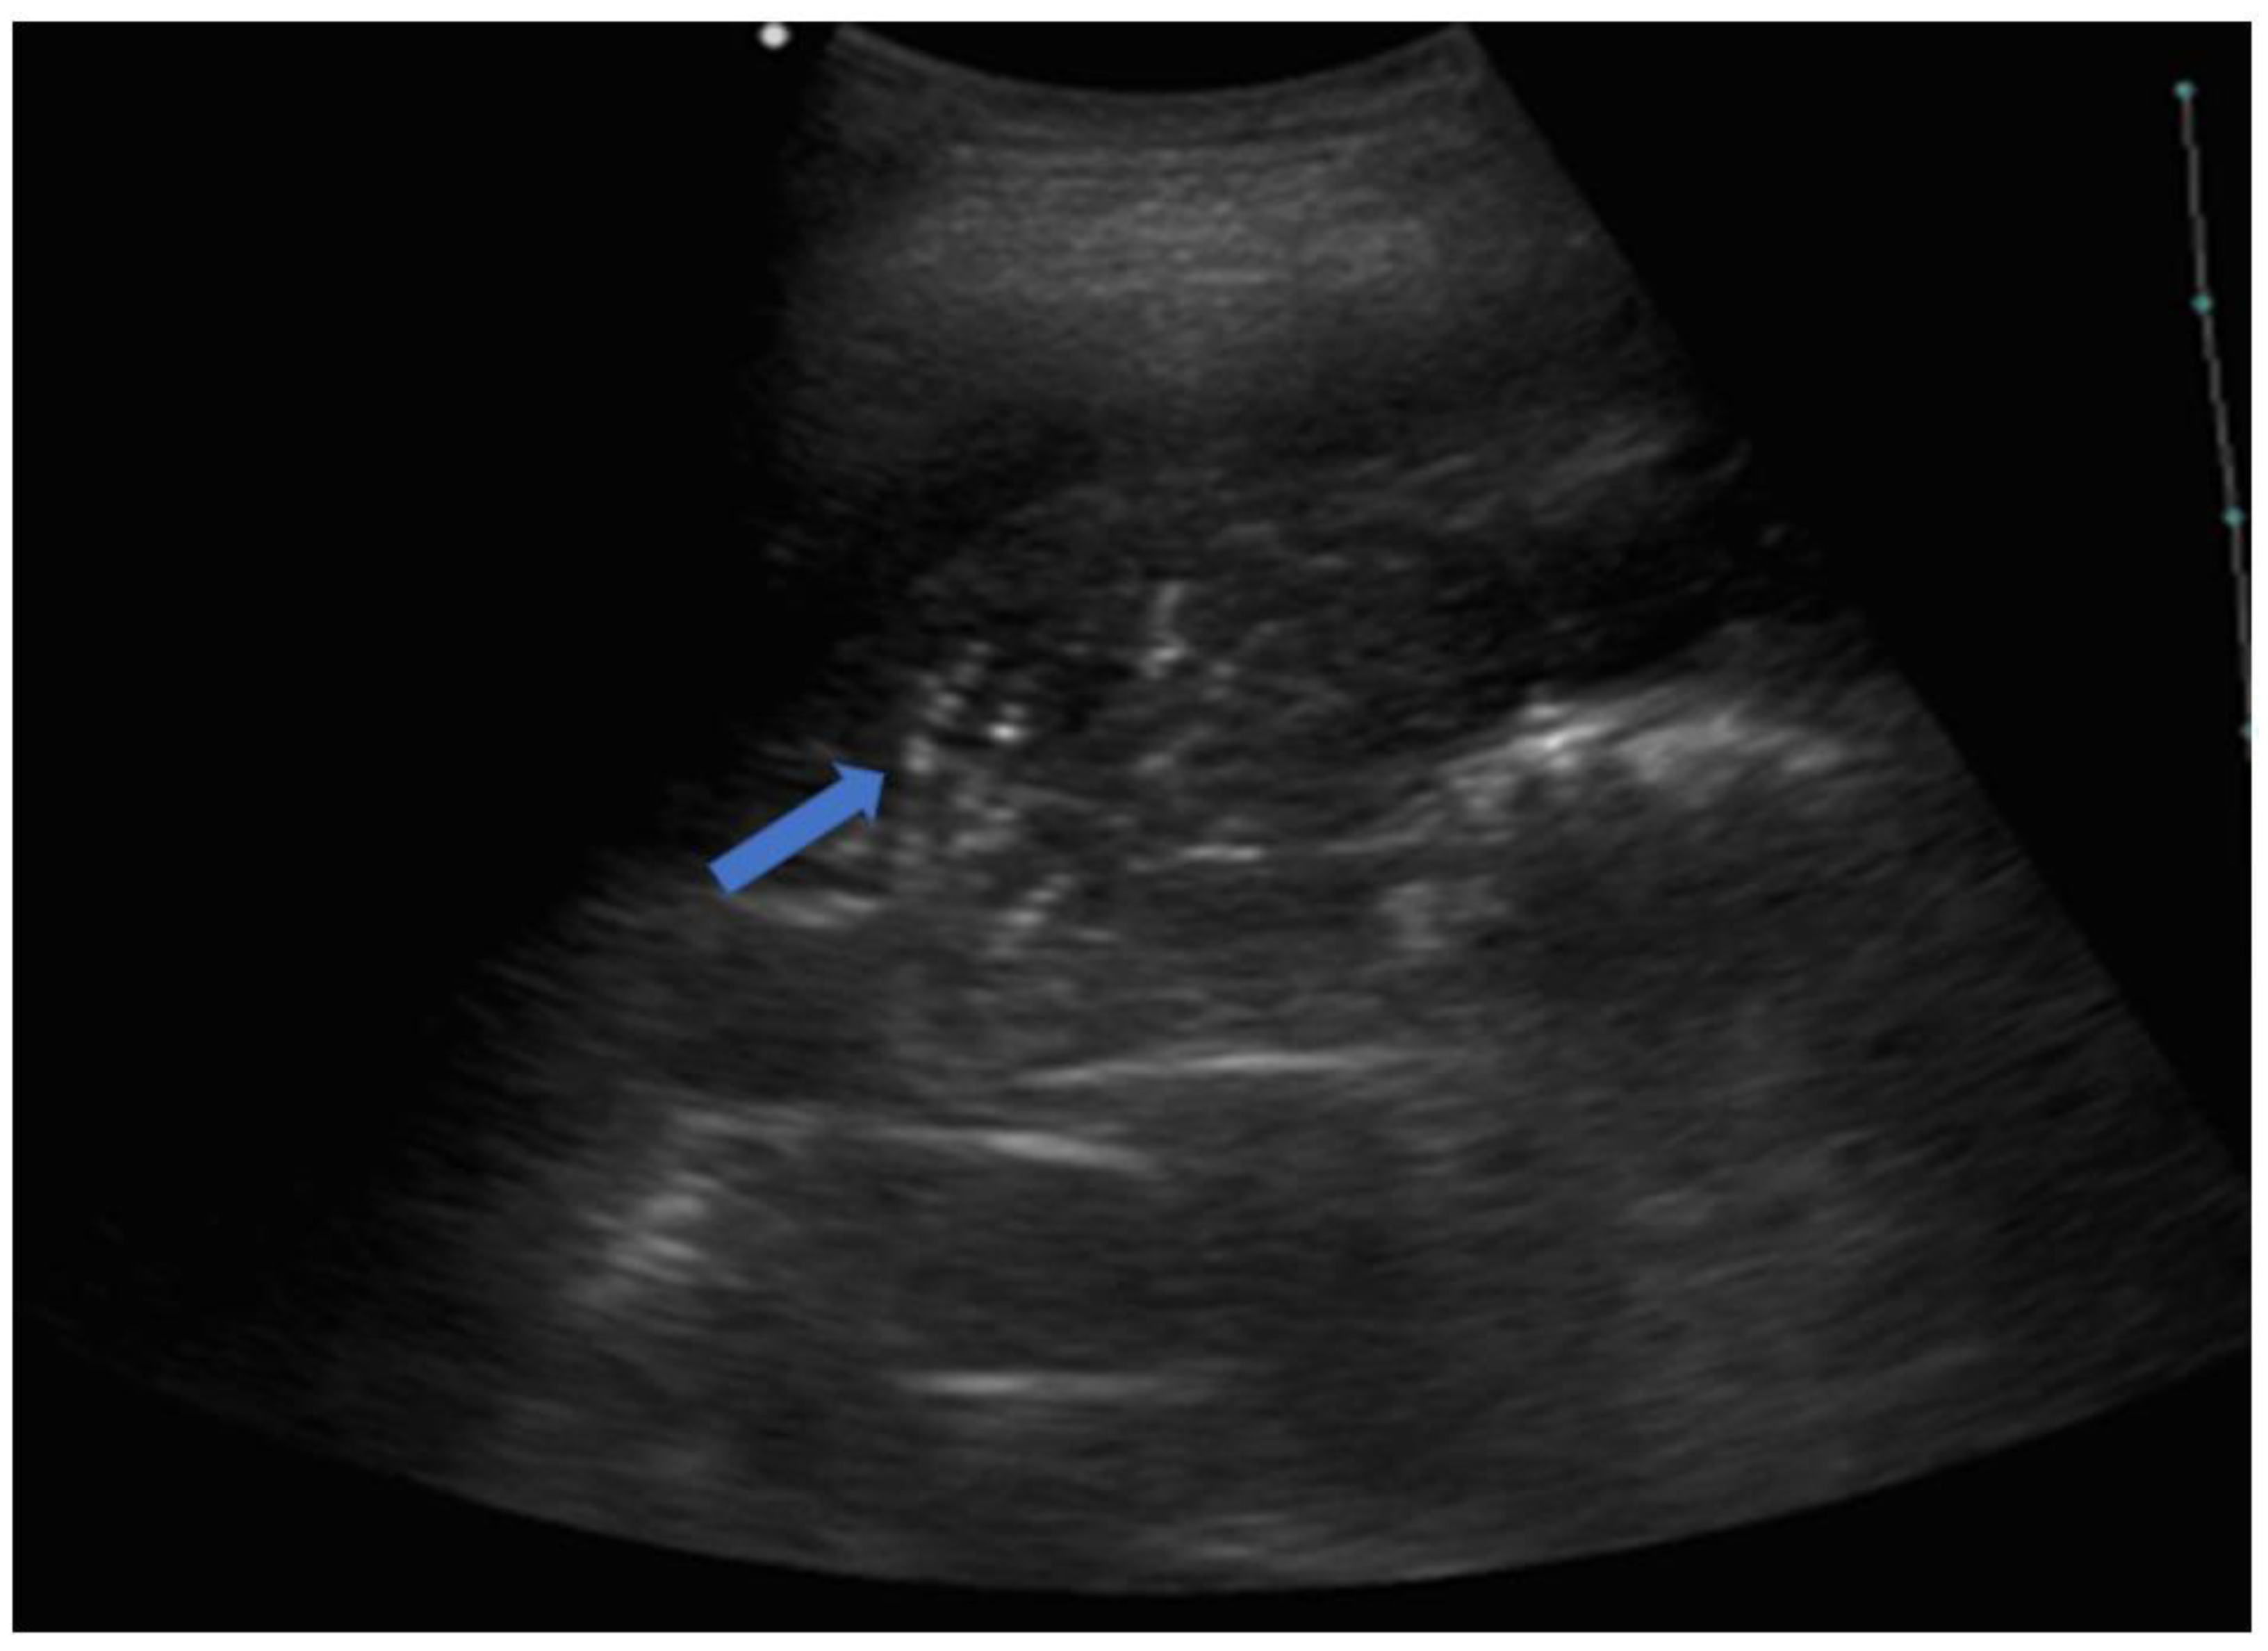

5.2. Lung Consolidations